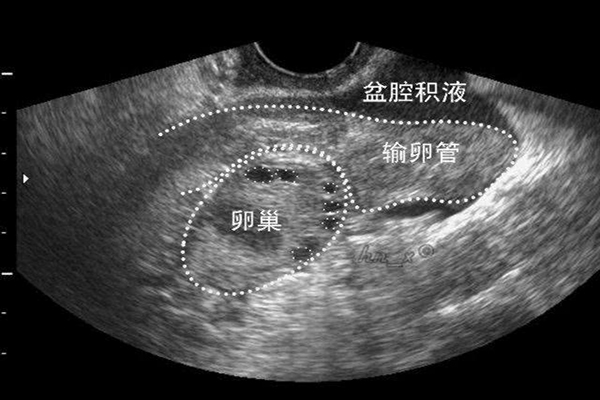

专家全面解读盆腔积液是怎么回事

近年来,盆腔内疾病发病率升高,越来越多的女性受到妇科问题的困扰,而盆腔积液也是其中的一种。盆腔积液是妇科问题的一种表现,少量的积液临床无法诊断,只能通过超声检查..